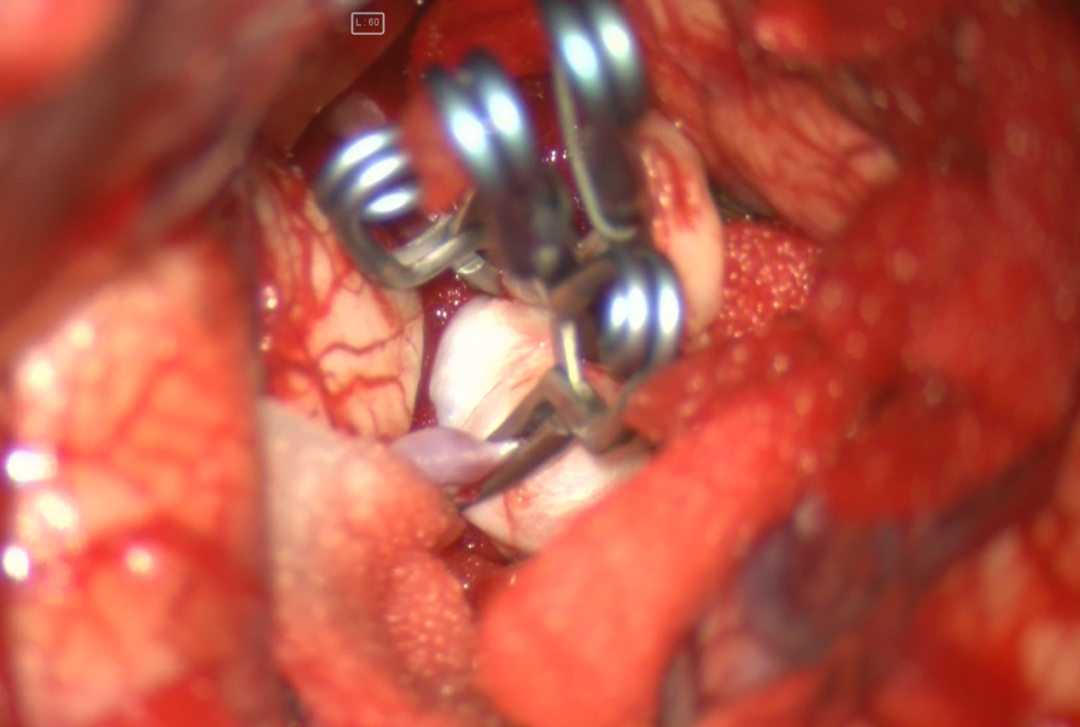

术前诊断:

术中电生理未见明显异常,因此未进行进一步血流重建处理。